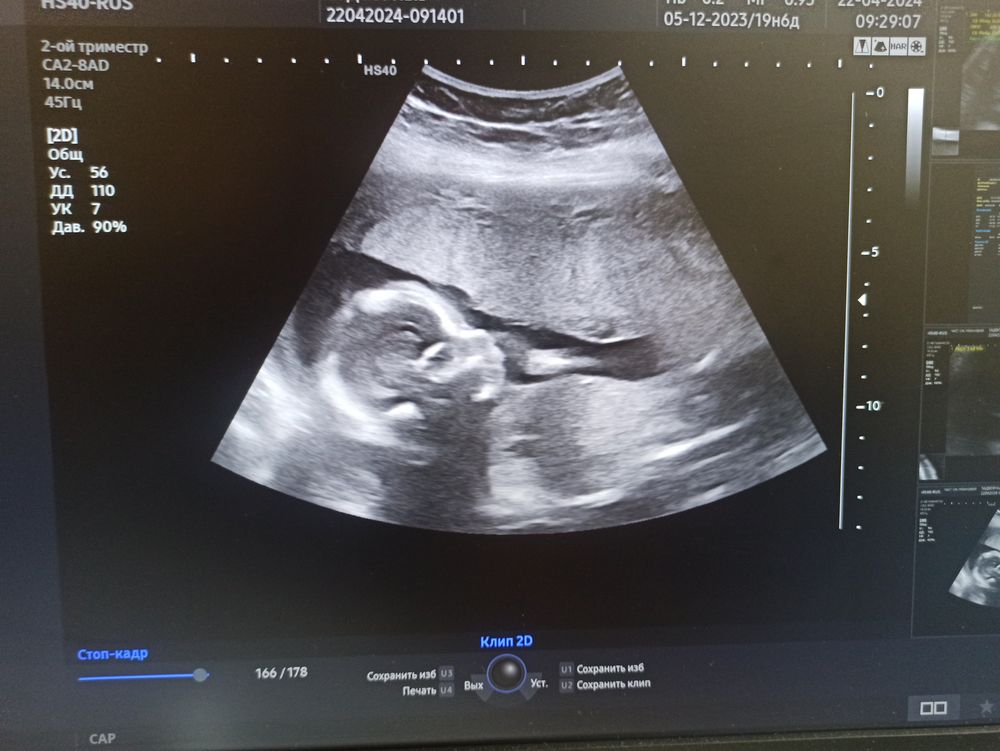

Два УЗИ в 19 недель ставят разный пол, может кто может рассудить?

Вроде бугорков не видно...

В 19 над уже не бугорки ищут. А половые губы или пенис. На фото у вас вообще голова )) сходите еще раз к другому специалисту через недельку. Бывает лежит неудобно, не получается нормально вывести область попы. За неделю подрастет и положение поменяет.

На снимке видно вообще только профиль головки